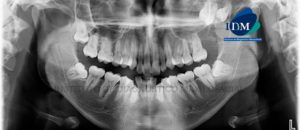

Paciente de 70 años acude al Instituto de Diagnóstico Maxilofacial para evaluación imagenológica indicada para la colocación de implantes. A la evaluación de la radiografía